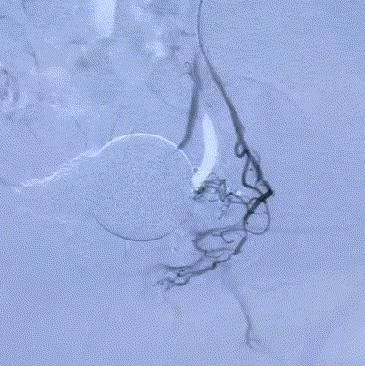

随後,李旭丹主任攜手胡志華主任爲患者實施介入治療,采用改良Seldinger法穿刺股動脈,在DSA引導下經動脈自然腔道,将微導管分别送達雙側髂内動脈進行造影,觀察雙側前列腺動脈分布情況,将微導管超選擇至雙側前列腺動脈,準确置入PVA栓塞材料,成功阻斷前列腺的營養供給,順利完成了治療。

△術前,可見前列腺供血豐富。